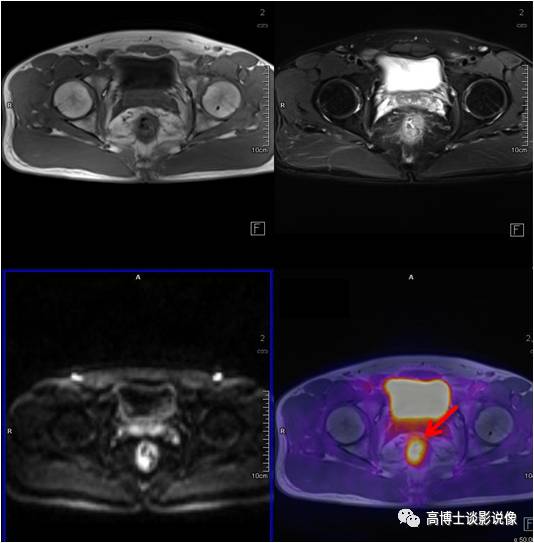

前列腺癌

老年男性,腹痛一周伴低热。PET/MR示前列腺左后方外周带见类圆形异常信号灶,直径约1.1cm,FDG摄取稍增高。之后穿刺证实为前列腺癌。

点评

前列腺癌高峰年龄是70~80岁,早期常无症状,血化验PSA升高,可以帮助筛查,但是有相当一部分前列腺炎症PSA也会升高,所以进一步鉴别需要依靠MRI/ PET,查出病变后还可以指导临床选择穿刺部位。

宫颈癌

中年女性,下腹部坠胀感1月。宫颈可见一类圆形软组织信号,大小约2.3cm× 2.5cm ,FDG摄取增高,病理诊断为宫颈鳞状细胞癌。

宫颈癌是最常见的妇科恶性肿瘤。高危型HPV持续感染是宫颈癌的主要危险因素。宫颈刮片细胞学检查是主要的筛查方法。PET对宫颈浸润癌的诊断准确性较高,对于术前分期和治疗后疗效评估很有价值。